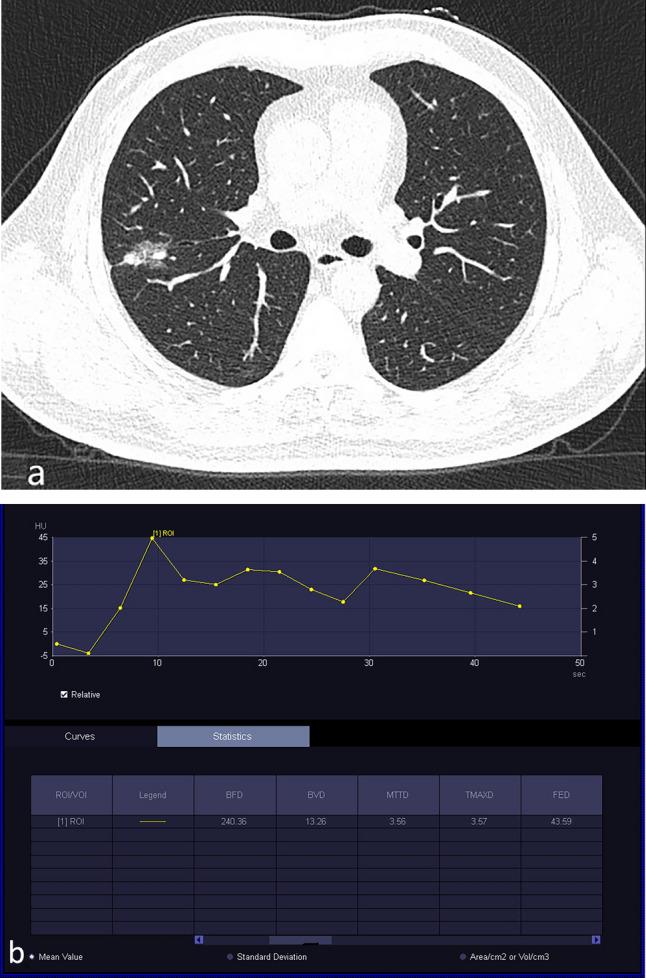

This study aimed to evaluate the value of low-dose dual-input computed tomography perfusion (CTP) imaging in the differential diagnosis of benign and malignant pulmonary ground-glass opacity nodules (GGO). A retrospective study was conducted in patients with GGO who underwent CTP in our hospital from January 2021 to October 2023. All nodules were confirmed via pathological analysis or disappeared during follow-up. Postprocessing analysis was conducted using the dual-input perfusion mode (pulmonary artery and bronchial artery) of the body perfusion software to measure the perfusion parameters of the pulmonary GGOs. A total of 101 patients with pulmonary GGOs were enrolled in this study, including 43 benign and 58 malignant nodules. The dose length product of the CTP (348 mGy.cm) was < 75% of the diagnostic reference level of the unenhanced chest CT (470 mGy.cm). The effective radiation dose was 4.872 mSV. The blood flow (BF), blood volume (BV), mean transit time (MTT), and flow extraction product (FEP) of malignant nodules were higher than those of the benign nodules (p < 0.05). The FEP had the highest accuracy for the diagnosis of malignant nodules (area under the curve [AUC] = 0.821, 95% confidence interval [CI]: 0.735-0.908) followed by BV (AUV = 0.713, 95% CI 0.608-0.819), BF (AUC = 0.688, 95% CI 0.587-0.797), and MTT (AUC = 0.616, 95% CI 0.506-0.726). When the FEP was ≥ 19.12 mL/100 mL/min, the sensitivity was 91.5% and the specificity was 62.8%. To distinguish between benign nodules and malignant nodules, the AUC of the combination of BV and FEP was 0.816 (95% CI 0.728-0.903), whereas the AUC of the combination of BF, BV, MTT, and FEP was 0.814 (95% CI 0.729-0.900). Low-dose dual-input perfusion CT was extremely effective in distinguishing between benign from malignant pulmonary GGOs, with FEP exhibiting the highest diagnostic capability.

本研究旨在评估低剂量双输入计算机断层灌注(CTP)成像在鉴别肺磨玻璃密度结节(GGO)良恶性中的价值。本回顾性研究纳入了 2021 年 1 月至 2023 年 10 月在我院行 CTP 的 GGO 患者。所有结节均经病理分析证实或随访中消失。采用体部灌注软件的双输入灌注模式(肺动脉和支气管动脉)对肺 GGO 的灌注参数进行后处理分析。本研究共纳入 101 例肺 GGO 患者,其中良性 43 例,恶性 58 例。CTP 的剂量长度乘积(348 mGy.cm)<未增强胸部 CT 诊断参考水平(470 mGy.cm)的 75%。有效辐射剂量为 4.872 mSV。恶性结节的血流量(BF)、血容量(BV)、平均通过时间(MTT)和血流提取产物(FEP)均高于良性结节(p<0.05)。FEP 对恶性结节的诊断具有最高的准确性(曲线下面积[AUC]为 0.821,95%置信区间[CI]:0.735-0.908),其次是 BV(AUC 为 0.713,95%CI 0.608-0.819)、BF(AUC 为 0.688,95%CI 0.587-0.797)和 MTT(AUC 为 0.616,95%CI 0.506-0.726)。当 FEP≥19.12 mL/100 mL/min 时,灵敏度为 91.5%,特异性为 62.8%。为鉴别良恶性结节,BV 和 FEP 联合的 AUC 为 0.816(95%CI 0.728-0.903),而 BF、BV、MTT 和 FEP 联合的 AUC 为 0.814(95%CI 0.729-0.900)。低剂量双输入灌注 CT 对鉴别肺 GGO 的良恶性非常有效,FEP 的诊断能力最高。